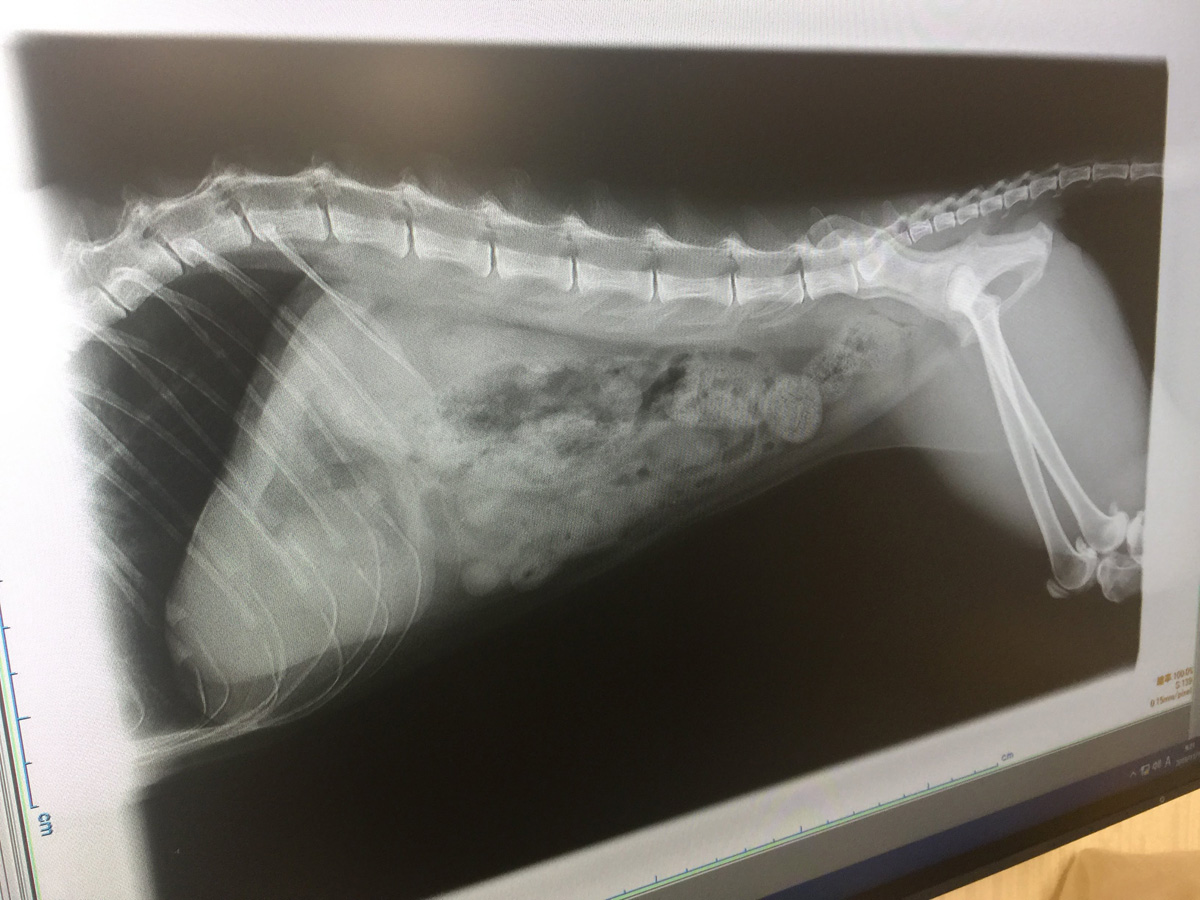

今日は特別に中身を少し公開しちゃうわね これを見たら必ず買わなきゃならないのよ